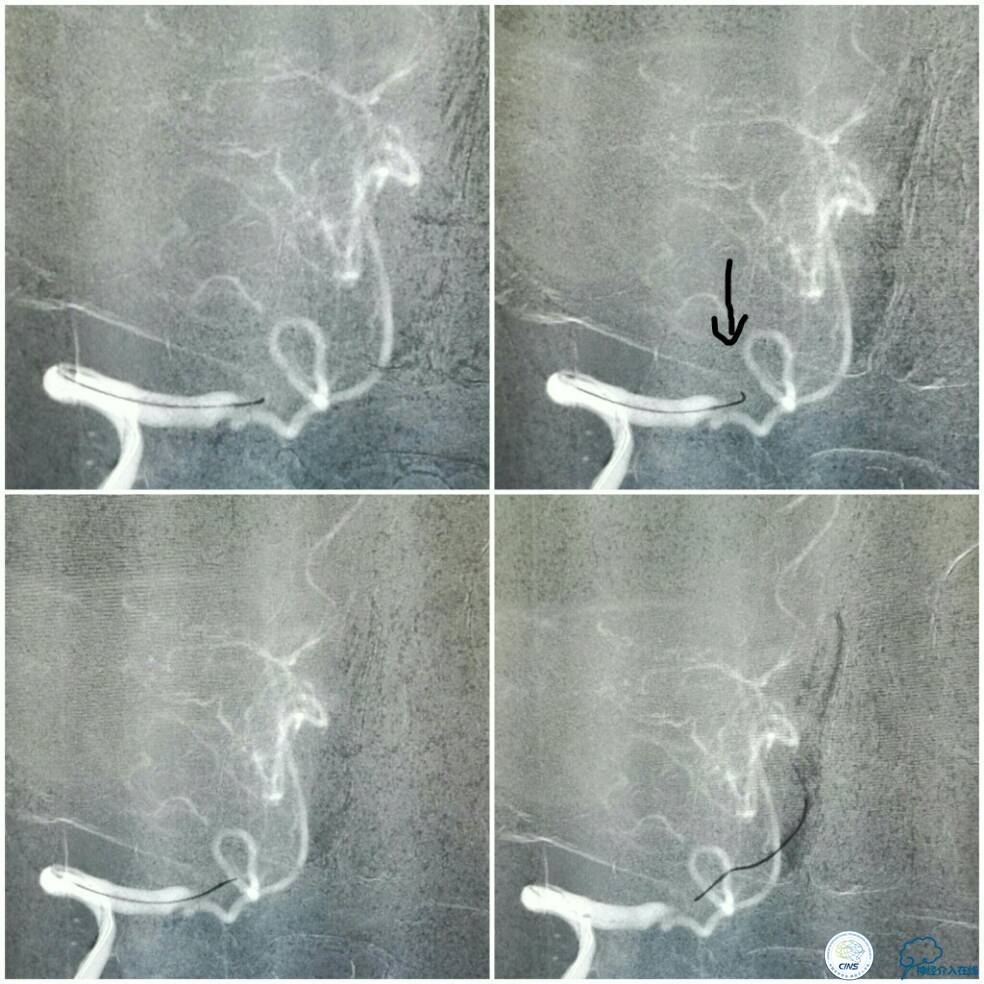

同期行DSA提示右椎动脉V4段发出右PICA后未见顺行显影(图2),左椎动脉V4段-基底动脉汇合处重度狭窄(图3),前循环向后循环的未见明显代偿(图4)。

全麻下双股动脉穿刺,分别置入6F及5F动脉鞘。6F导引导管置于右椎动脉V2段,Traxcess 微导丝与Echelon 10微导管同轴,经多次尝试后送达基底动脉(图8);操作过程中见微导丝头端打折变向,此时手控导丝有阻力感,考虑是闭塞病变的近心端(图8箭头),当微导丝越过闭塞段进入血栓,此时微导丝及微管前行无明显阻力。

图8

微导管造影证实在基底动脉真腔后,交换技术送入Transend微导丝(0.014″300 cm)至左侧大脑后动脉P1段,送入Gateway球囊(2.0 mm×9.0 mm)从闭塞段远端向近心端扩张4次,扩张完造影示右椎动脉V4段无再通(图9)。

图9